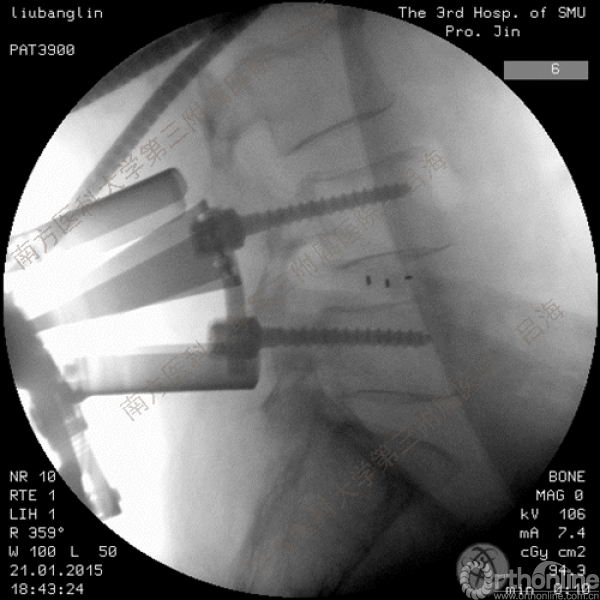

随着社会老龄化进程加快,胸腰椎退行性病变的治疗已经成为脊柱学术界的一个热点话题。MIS-TLIF手术可以治疗多种不同的胸腰椎退行性疾病,南方医科大学第三附属医院吕海教授结合病例为我们一一展示了该术式在治疗不同胸腰椎疾病时的具体手术过程。